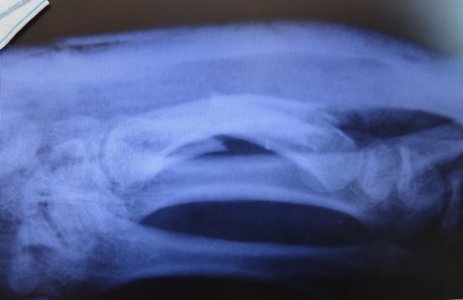

Сказал ходить 5 недель + кальцемин 2 р. в день и контрольный снимок через 7 дней, вот он: